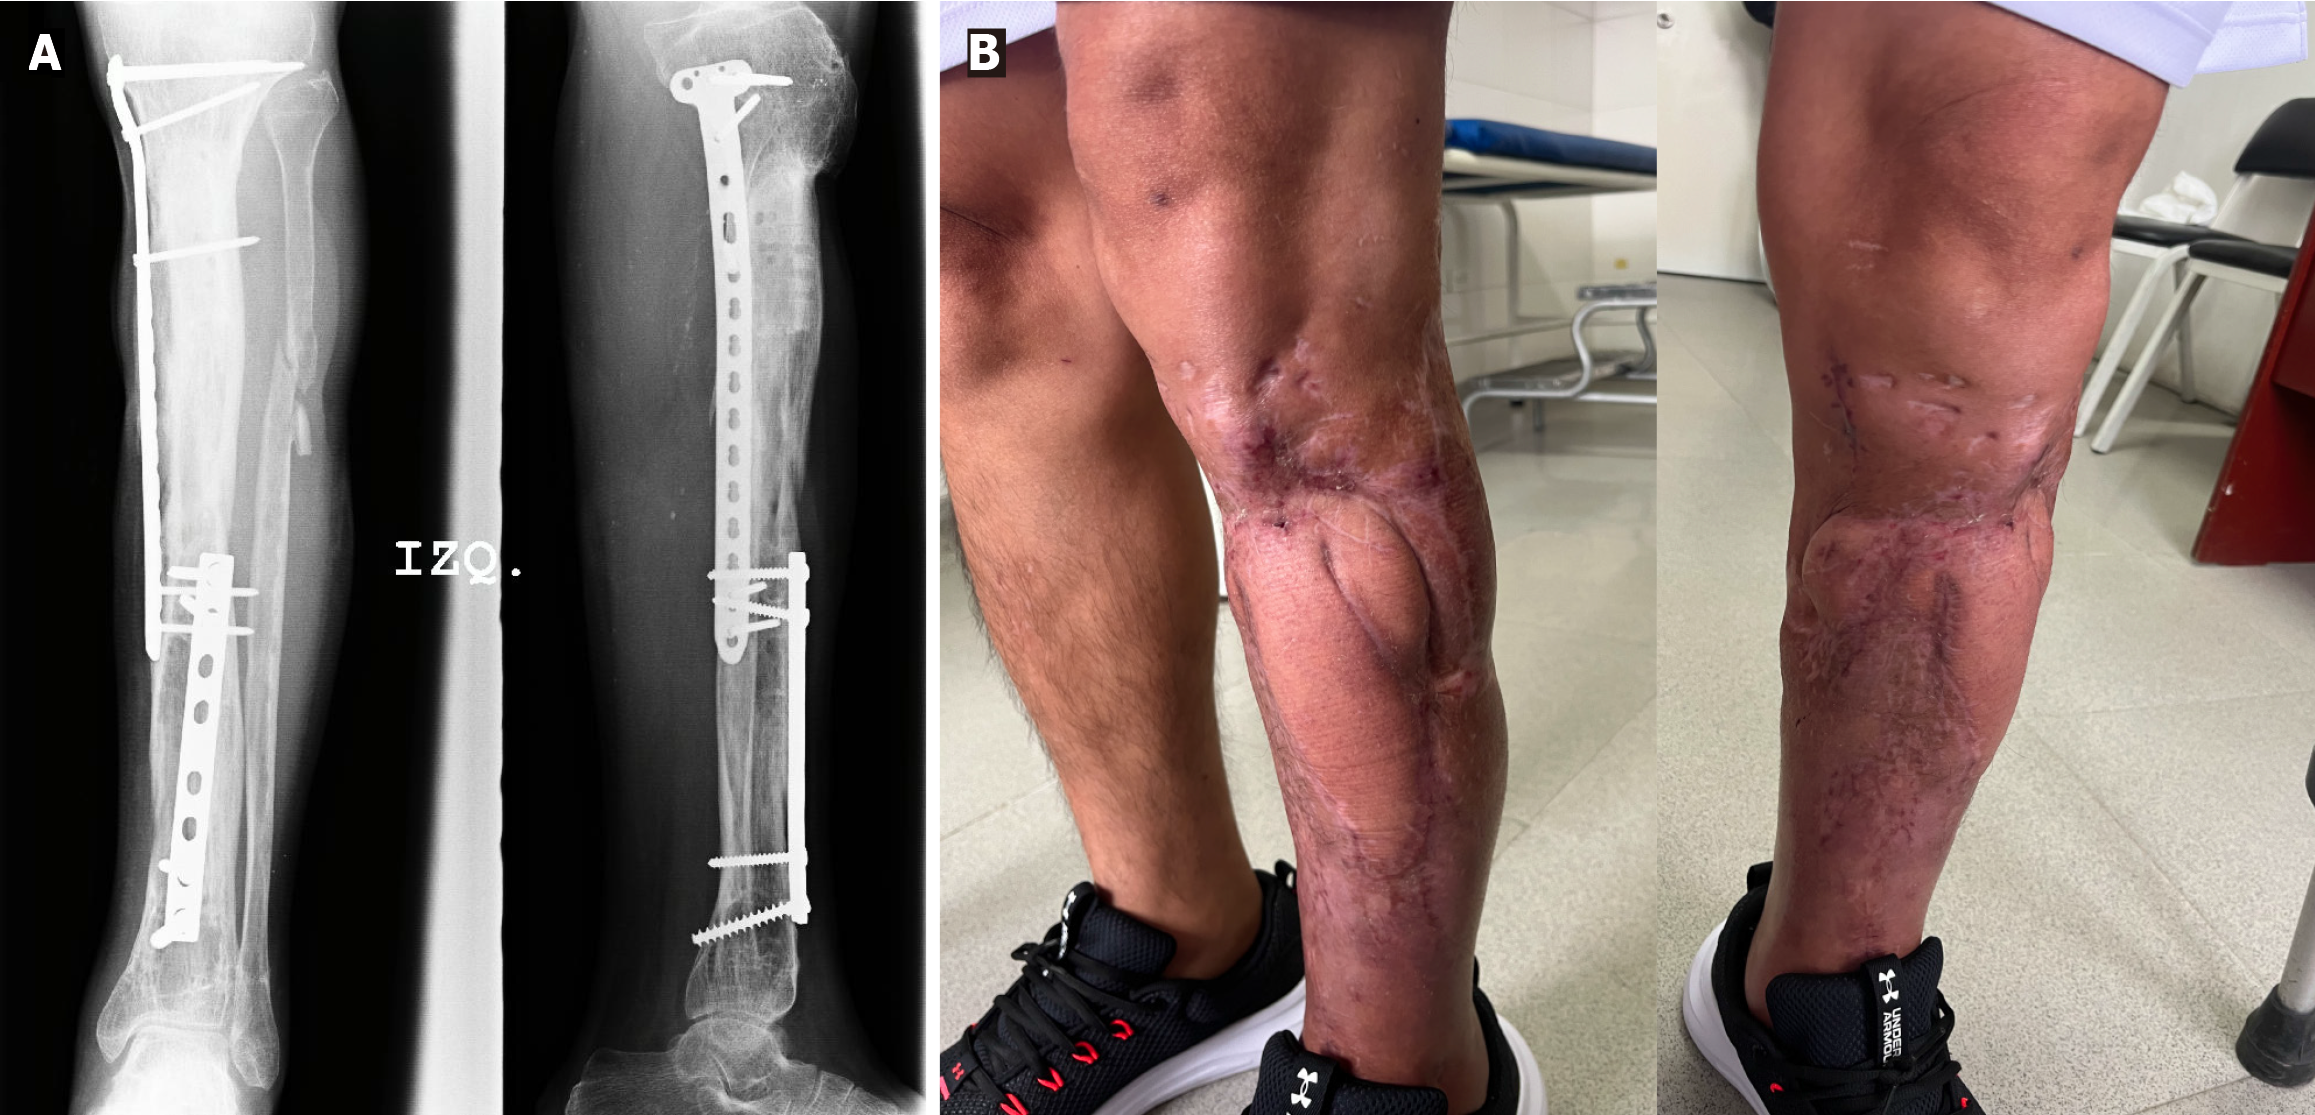

The patient underwent radical debridement of nonviable bone and soft tissue (Figure 3), and he received negative pressure therapy. An anterolateral thigh free flap was used for the reconstruction of the soft-tissue defect. An 8-week course of antibiotic therapy was administered, consisting of intravenous cefazolin (1 g every 8 hours) combined with gentamicin (80 mg every 8 hours) for the first 5 weeks, followed by cefazolin (500 mg every 6 hours) for an additional 3 weeks. Trifocal bone transport was performed with a circular Ilizarov fixator (Figures 4 and 5). The axis deformity was corrected simultaneously (Figure 6). Locking compression plates were applied to protect the bone regeneration after removal of the external fixation (Figure 7).

After 17 months bone regeneration and corticalization was observed. Six months after the frame removal, the patient was asymptomatic with no pain or infections. The patient had also returned to work. Functional recovery was confirmed by excellent Association for the Study and Application of the Method of Ilizarov bone and functional scores.

Trifocal bone transport is particularly useful for massive defects (> 6 cm) because it reduces the duration of external fixation and accelerates consolidation[3,4]. Patients undergoing trifocal bone transport have reported some complications including pin site infections, soft-tissue invagination, deformity, and the psychological burden of long external fixation durations. Sequential conversion to locking plates enhances corticalization and prevents refracture[5]. We also observed these outcomes in our patient.